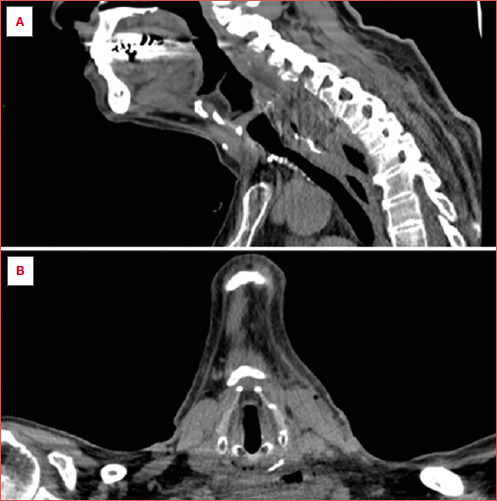

Abstract Image